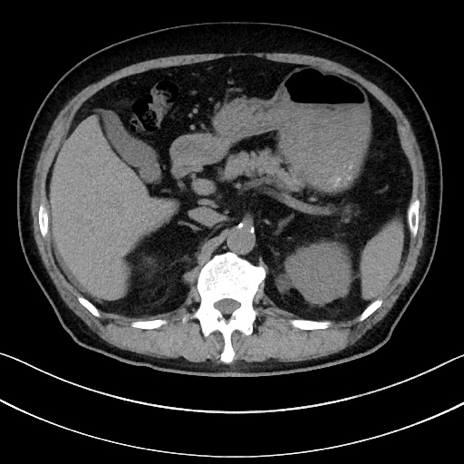

症例15(横断像)

【症例】70歳代男性

【主訴】腹痛

【現病歴】今朝から腹痛あり。全体的に痛い。特に左上の方。排ガスが今日はない。冷や汗が出る。

【既往歴】直腸癌術後

【身体所見】左側腹部〜上腹部に圧痛あり。腹膜刺激症状明らかなではない。軽度反跳痛。左下腹部に術後瘢痕あり。

【データ】WBC 7700、CRP 0.02